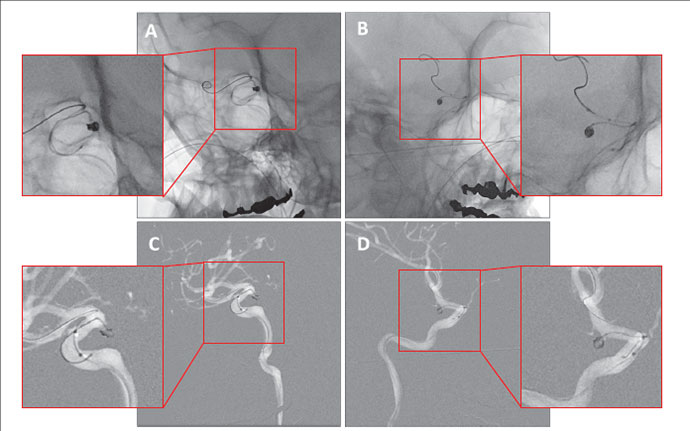

Trinias在脑动脉瘤弹簧圈栓塞术中的性能

更加清晰的图像辅助神经科介入手术轻松自如!